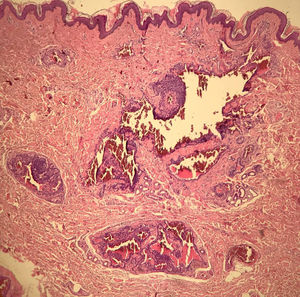

À dermatoscopia, observamos lagunas arroxeadas e circunscritas por um halo pálido ao lado de uma área rosada sem estruturas (fig. 2). Foi realizada exérese cirúrgica da lesão e houve confirmação histopatológica de tumor glômico extradigital (TGE). A histologia evidenciou ninhos intradérmicos de células monomórficas, com núcleo arredondado, organizados em cordões, únicos ou múltiplos ao redor de estruturas vasculares (fig. 3). Ao centro do corte, observamos um desses ninhos com tamanho exuberante em relação aos demais (fig. 4). Não houve recidiva após dois anos de seguimento.

O TGS é composto por ninhos de células glômicas uniformes e agrupados, sem vascularização proeminente ou tecido muscular liso exuberante. Os tumores com diferenciação e presença importante de tecido muscular liso são subclassificados como glomangiomiomas. Os glomangiomas apresentam ninhos intradérmicos de células glômicas, monomórficas, com núcleo arredondado, organizados em cordões, únicos ou múltiplos ao redor de estruturas vasculares exuberantes.1,2,4,6 A descrição é compatível com a do caso em questão (fig. 3). A prevalência de glomangiomas é maior dentre os tumores extradigitais.1

O achado dermatoscópico, área arroxeada sem estruturas, descrito anteriormente na literatura, foi encontrado em lesões de TGS formados por uma massa tumoral coesa com componente celular mais abundante em relação aos espaços vasculares. Essa organização histológica se reflete no achado dermatoscópico encontrado.4 Nos glomangiomas, as grandes estruturas vasculares circundadas por cordões celulares delicados podem se distanciar e destacar individualmente (fig. 4), originando as lagunas arroxeadas descritas por este trabalho. Logo, acreditamos que seja não apenas um achado dermatoscópico associado aos TGE, mas também que indique um subtipo específico: o glomangioma. Apesar da limitação das conclusões a partir deste único caso, esse novo achado dermatoscópico pode complementar a investigação e aumentar a acurácia do diagnóstico dos TGE.